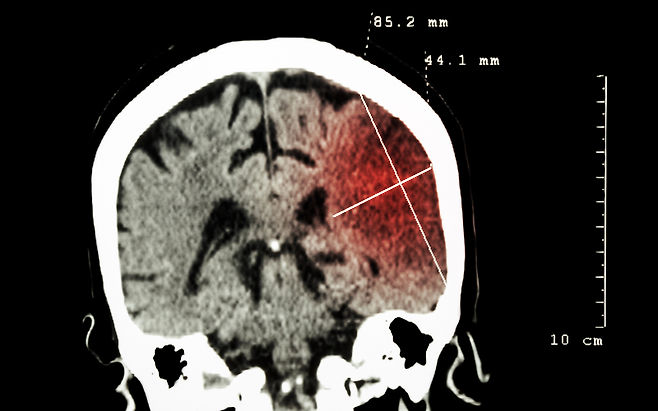

뇌경색은 뇌로 가는 혈관이 막혀 뇌세포가 손상되는 무서운 질환입니다. 특히 초기 전조 증상을 모르고 방치하면 단 몇 분 만에 생명이 위태로워질 수 있죠.